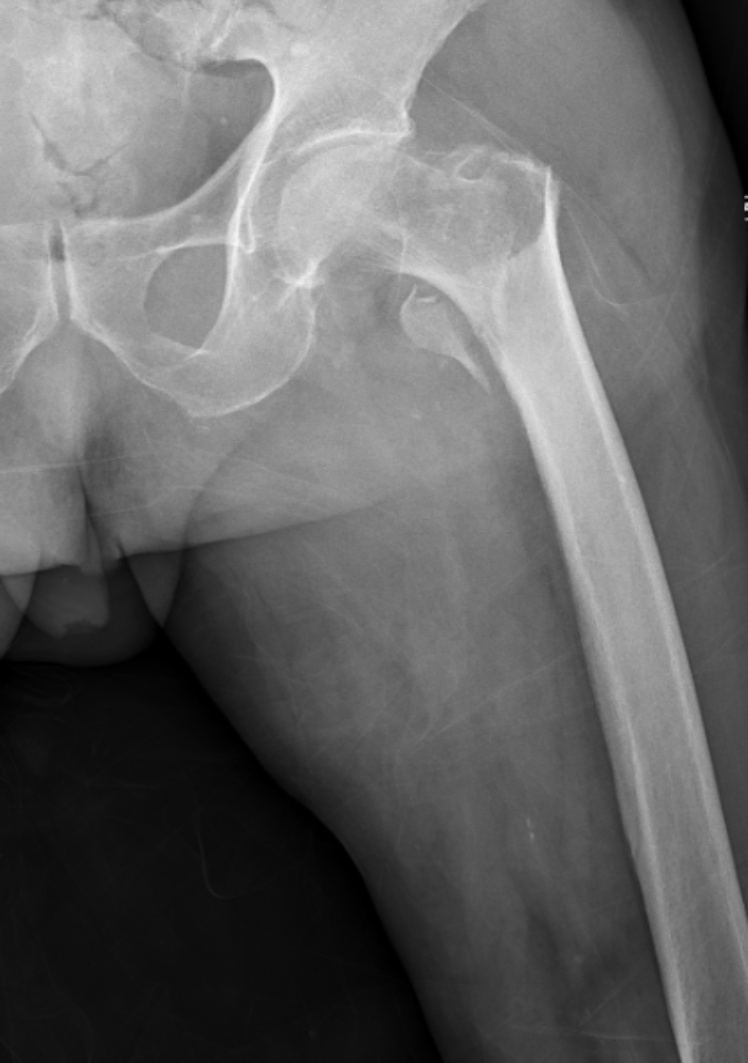

典型病例影像学表现见图1~10。图1为86岁女性右侧股骨转子间骨折(Evans Ⅲ型)患者,术前X线示骨折断端部分错位,术后X线示骨折位置可以及假体位置良好;图2显示了一名81岁男性患者,诊断为左侧股骨转子间骨折,类型为Evans V型,合并股骨干陈旧性骨折。患者接受了生物型加长柄半髋关节置换手术,并进行了股骨近端的钢丝捆扎内固定。术后X线示假体位置良好,股骨近端予钢丝捆扎固定;图3为87岁女性左侧股骨转子间骨折(Evans V型)患者,术后X线示假体位置良好,股骨大小转子骨折位置可,钢丝捆扎固定在位有效;图4为75岁女性左侧股骨转子间骨折(Evans V型)患者,术前X线示左侧股骨转子间骨折PFNA术后、骨折未愈合、内固定断裂。术后假体匹配良好,股骨近端钢丝内固定稳定可靠;图5为75岁男性左侧股骨转子间骨折(Evans IV型)患者,术后股骨大转子出现轻度位移,假体位置正常。图6为87岁男性左侧股骨转子间骨折(Evans V型)患者,给予DAA入路加长柄半髋关节置换,术前X线片,清晰地显示出左侧股骨转子间的骨折情况,术后X线影像,显示股骨的大小转子骨折位置良好,钢丝内固定装置在位稳定,假体位置良好;图7为77岁女性右侧股骨转子间骨折(Evans V型)患者,术前X线片显示右侧股骨转子间存在骨折且股骨大小转子均有累及和移位,术后X线片显示股骨小转子轻度移位,内固定装置位置稳定,假体位置良好;图8为70岁男性左侧股骨转子间骨折(Evans III型)患者,术前的X线片,清晰地显示了左侧股骨转子间的骨折情况,股骨近端髓腔钙化灶,术后假体位置满意;图9为77岁女性右侧股骨转子间骨折(Evans V型)患者,术前X线片,显示右侧股骨转子间及转子下部位骨折情况。术后假体匹配良好;图10为71岁男性右侧股骨颈骨折(Evans IV型)患者,术前X线片,显示右股骨转子间骨折的情况;术后X线表明股骨的大转子和小转子骨折位置保持良好,内固定装置稳固,术后假体位置正常。

(a) (b)

Figure 2. An 81-year-old male patient with left intertrochanteric fracture of the femur (Evans type IV). (a) Before surgery; (b) After surgery

2. 81岁男性左侧股骨转子间骨折(Evans Ⅳ型)患者。(a) 术前;(b) 术后